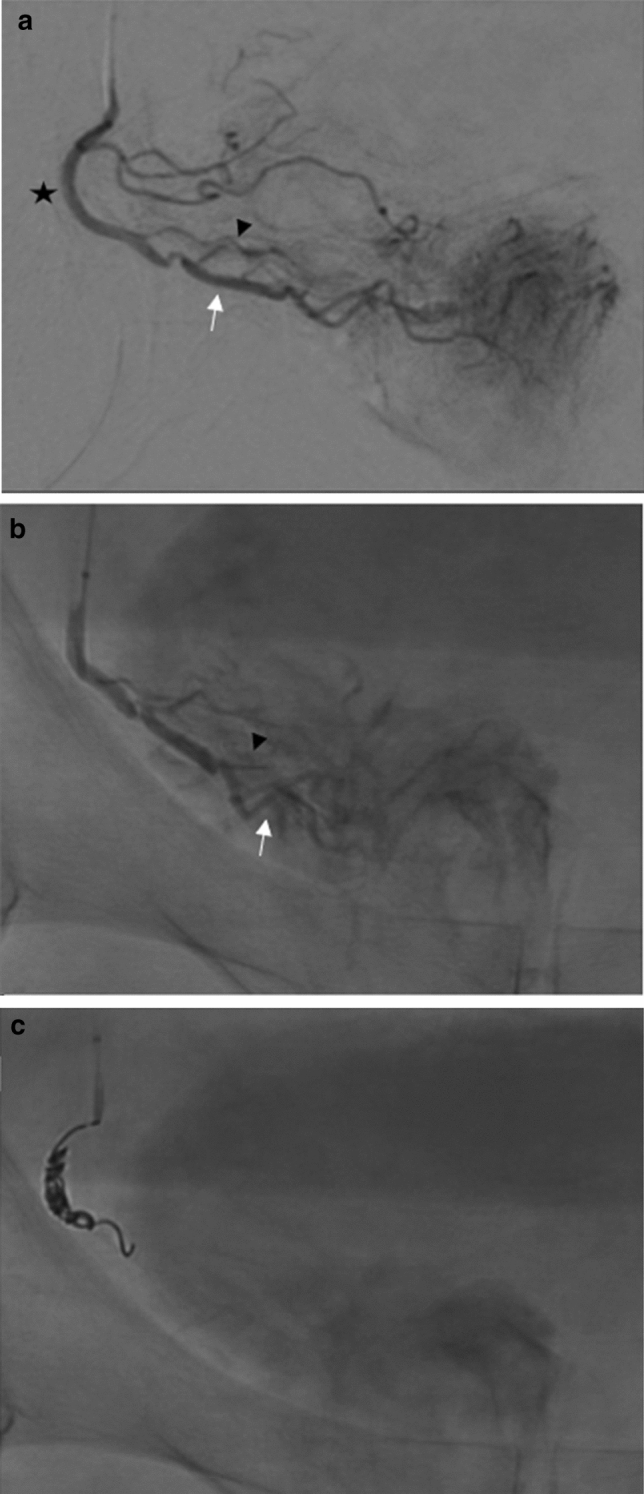

Fig. 1.

a Selective right PA angiogram under ipsilateral oblique projection. Prostatic artery branches arising from a common trunk. Prostatic artery (black star); anteromedial branch (white arrow); posterolateral branch (black arrowhead) b Particle embolization of the right PA via the microcatheter proximal to the bifurcation of the anteromedial and posterolateral branches to near stasis c Placement of detachable microcoils in the right main PA with microcatheter in stable position proximal to the bifurcation of the anteromedial and posterolateral branches